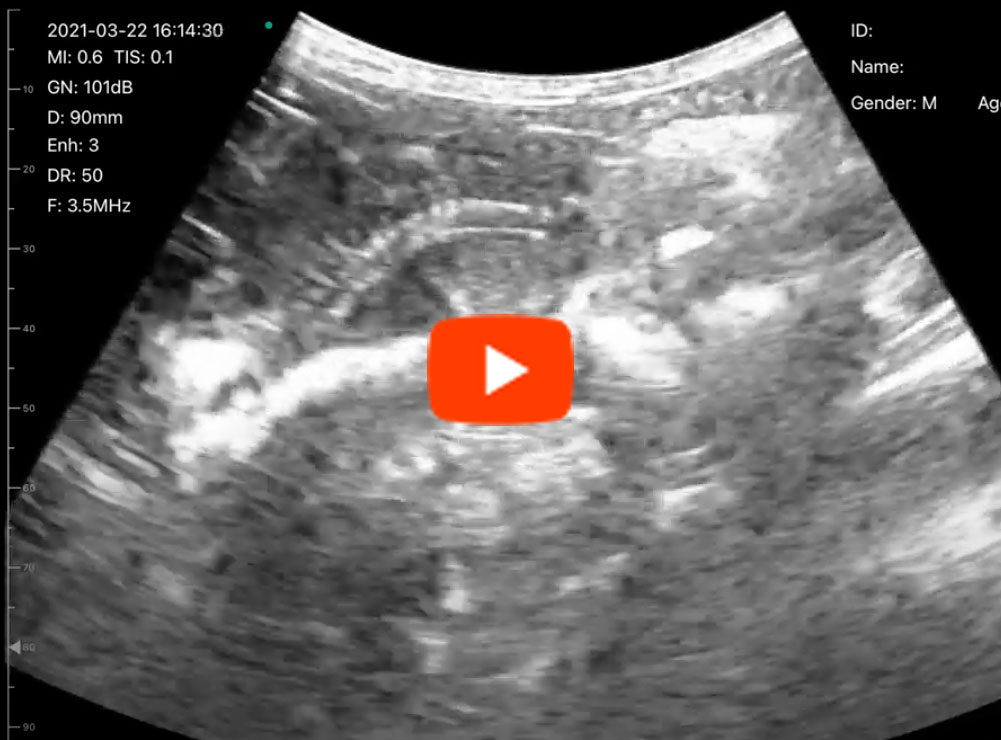

C6C動画1

C6C動画2

C6C動画3

C6C動画4